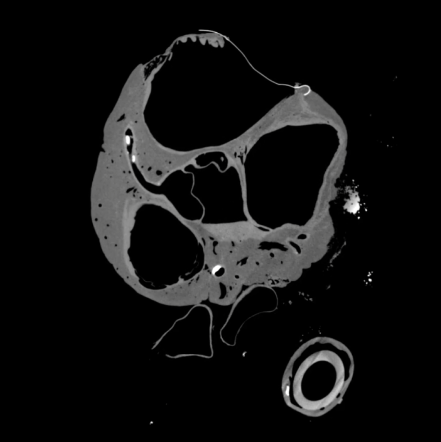

Short Axis Stack 4 Chamber Stack

A two chamber stack shows one complete series of reconstructed images from a microCT scan. These images are in a plane aligned to the long axis of the left ventricle with a slice thickness corresponding to the pixel resolution. As these videos play you will see the left side and the right side of the heart independently of each other separated by the septum in the middle of the sequence. Each heart video will have its own resolution.